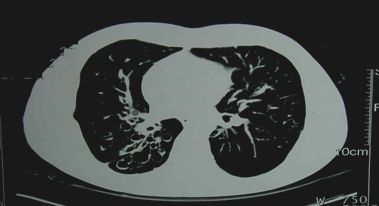

②胸部CT

可顯示管壁增厚的柱狀擴(kuò)張或成串成簇的囊狀改變。高分辨CT(HRCT)(可確診)。

『答案解析』胸部CT可顯示管壁增厚的柱狀擴(kuò)張或成串成簇的囊狀改變。高分辨CT(HRCT)(可確診),支氣管造影:由于該檢查為創(chuàng)傷性檢查,已被CT取代,所以最有確診價(jià)值的檢查選擇D.